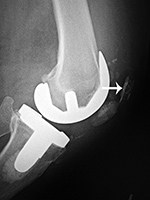

| Posterior cruciate retaining total knee arthroplasty (TKA) |

Posterior cruciate substituting total knee prosthesis and patellar resurfacing. |

| 68 year-old woman treated for severe left knee osteoarthritis |

Note the large distal femoral box. There is a surgical drain in the suprapatellar space. |